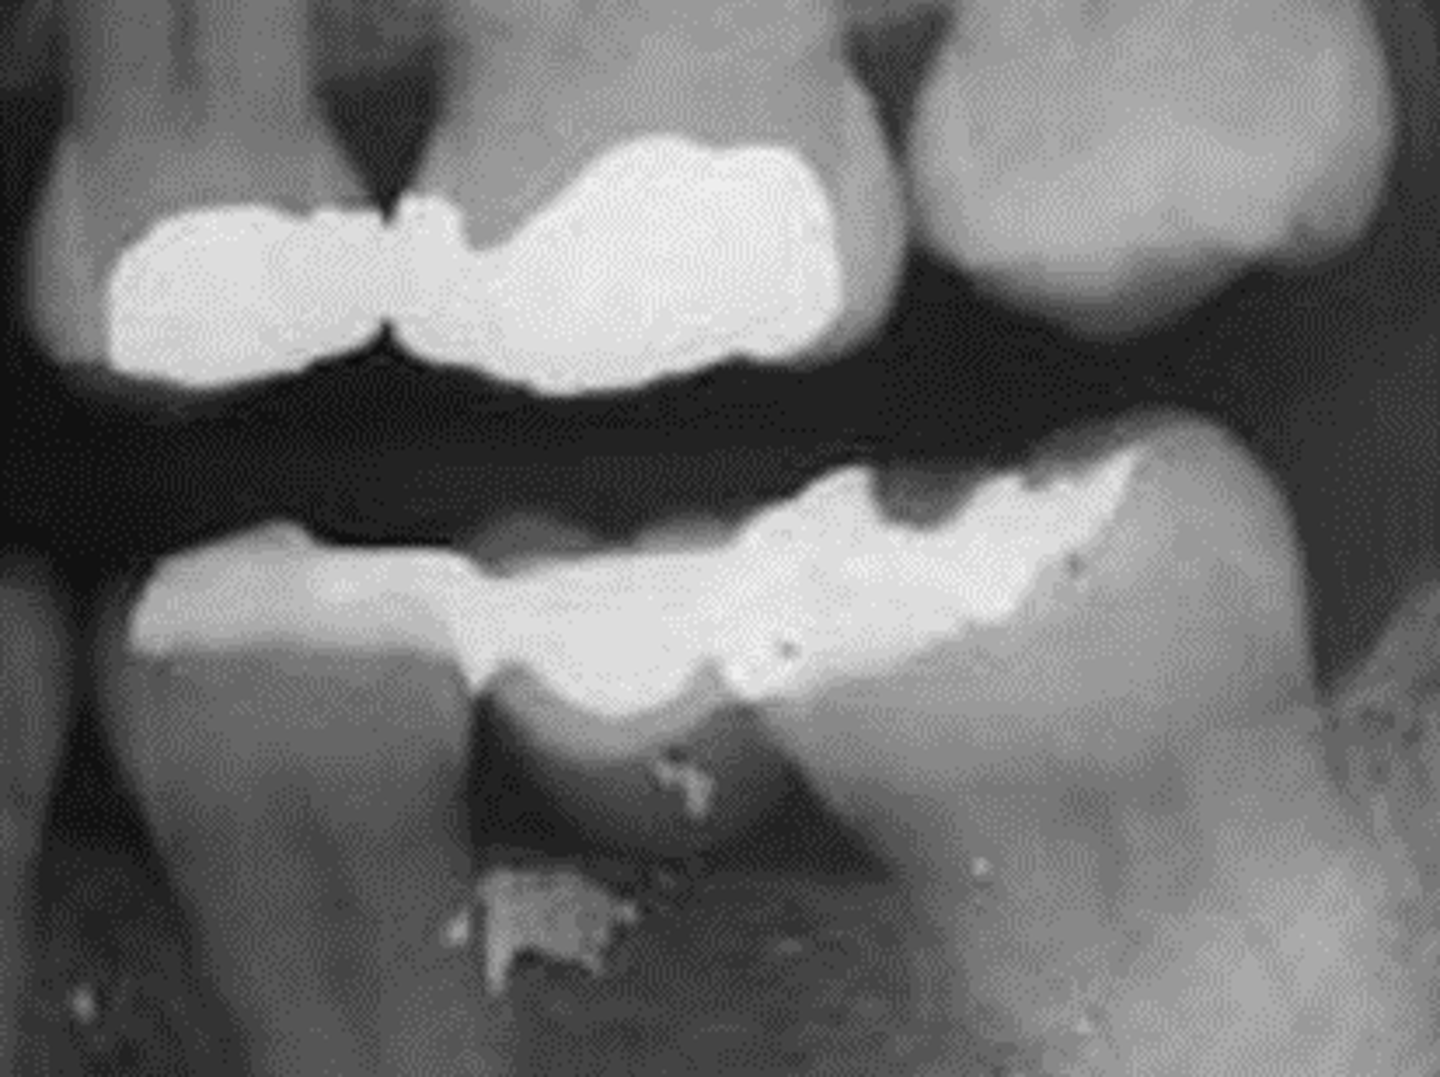

black film

can be caused by overdeveloping, developer too hot, or exposure to white light after x-ray exposure

exhausted chemicals

cause film to be too light, fogged, or tinted brown

exhausted fixer pictured